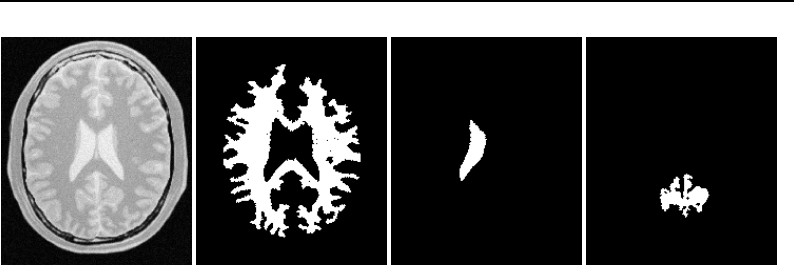

The National Library of Medicine Insight Segmentation and Registration Toolkit, shortened as the

Insight Toolkit (ITK), is an open-source software toolkit for performing registration and segmenta-

tion. Segmentation is the process of identifying and classifying data found in a digitally sampled

representation. Typically the sampled representation is an image acquired from such medical instru-

mentation as CT or MRI scanners. Registration is the task of aligning or developing correspondences

between data. For example, in the medical environment, a CT scan may be aligned with a MRI scan

in order to combine the information contained in both.